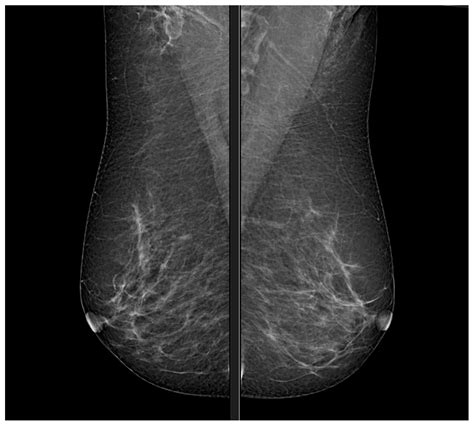

Interpreting normal mammogram images involves a systematic approach to ensure that no abnormalities are missed. Radiologists look for specific features that indicate normality:

• Uniform Density: The breast tissue should appear uniform in density, with no areas of increased or decreased density.

• No Masses: There should be no visible masses or lumps in the breast tissue.

• No Calcifications: There should be no calcifications, which are small deposits of calcium that can sometimes indicate the presence of cancer.

• No Architectural Distortions: The breast tissue should have a normal architecture, with no distortions or pulling of the tissue.

Radiologists also compare current mammogram images with previous ones to detect any changes over time. This comparison helps identify subtle abnormalities that may not be apparent in a single exam.